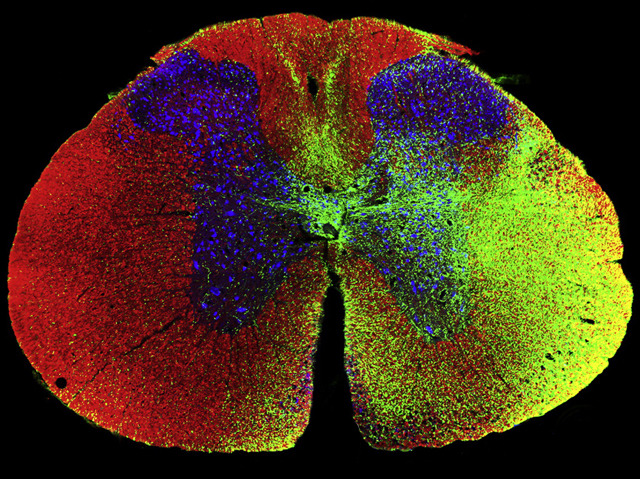

Christopher Reeve, the actor who still incarnates Superman for a whole generation, died in 2004 of complications ten years after crushing vertebrae in his neck while horse-riding. The accident snapped nerves in his spinal cord linking the brain to muscles in his chest and limbs, leaving him paralysed below the shoulders and unable to breathe unassisted. Befitting Superman, Reeve fought relentlessly for more research into stem cells' promise to re-grow nerves. Ten years on, biologists report increasingly successful experiments where stem cells grafted into damaged spines sprout extensive networks of nerve fibres. In this rat spine cross-section, human iPSC stem cells from an 86-year-old patient showcase the power of regenerative medicine as the cells unfurl long new fibres (green speckles) along the length of the spine – though stopping short of bridging the wound to restore motor function – but crucially, connecting to existing nerves. Superman, are you watching from planet Krypton?